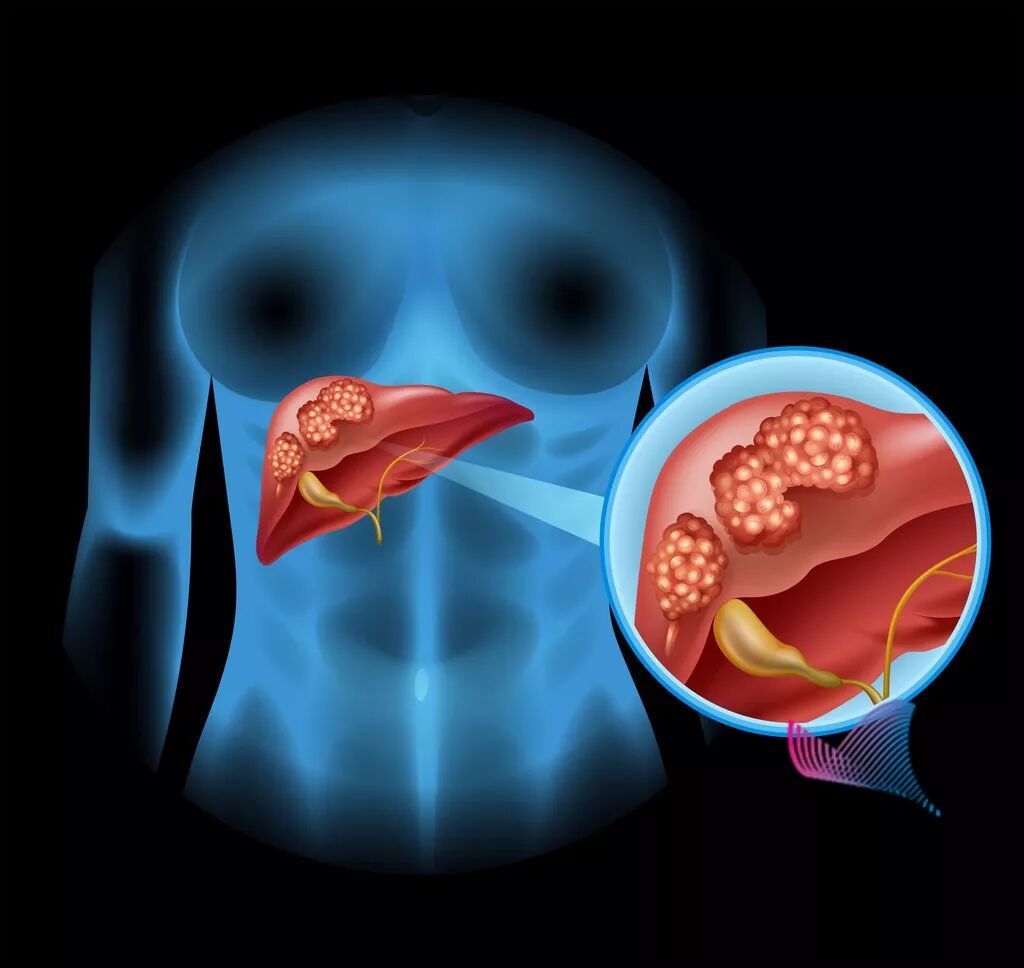

有一种癌症,隐蔽性强、发病率较高、生存率较低。在中国,80%的患者发现时已到中晚期。根据2019年1月国家癌症中心发布的最新一期全国癌症统计数据显示,肝癌发病率排名第四,死亡率排名第二。

俗话说“胃是喇叭,肝是哑巴”。肝癌不易发现又如此可怕,所以早发现早治疗成为关键。肝癌因隐秘性强,早期表现不明显,导致很多患者发现时就已到了中晚期,错过了最佳的治疗窗口。首先,肝脏隐藏在腹腔,被骨性器官保护,正常时不易触及,且仅肝脏表面有神经分布,当病变侵犯肝脏包膜时才产生疼痛感觉。所以,当肿瘤还没有长大或者距离包膜部位远,症状不明显或无不适感,绝大多数人都不会去医院就诊。

其次,对于正常人而言,一般只要有30%的肝脏就足以维持人体的正常运转,就不会表现出肝功能异常。所以,很多肝癌患者出现黄疸、腹水等症状时,已是中晚期。

肝区疼痛 肝区疼痛多呈持续性胀痛或钝痛,是肝癌晚期常出现的症状之一。肝肿大 大约90%以上的肝癌患者的肝脏呈进行性肿大,伴随着不同程度的压痛。肝硬化征象 如果肝癌患者伴有肝硬化门静脉高压,会出现腹水、静脉侧支循环形成等情况。全身性表现 肝癌患者多出现发热乏力、进行性消瘦、营养不良,以及恶病质等症状。

转移灶症状 如果发生了肺部、胸腔等处的转移,相应部位可能出现不适症状。